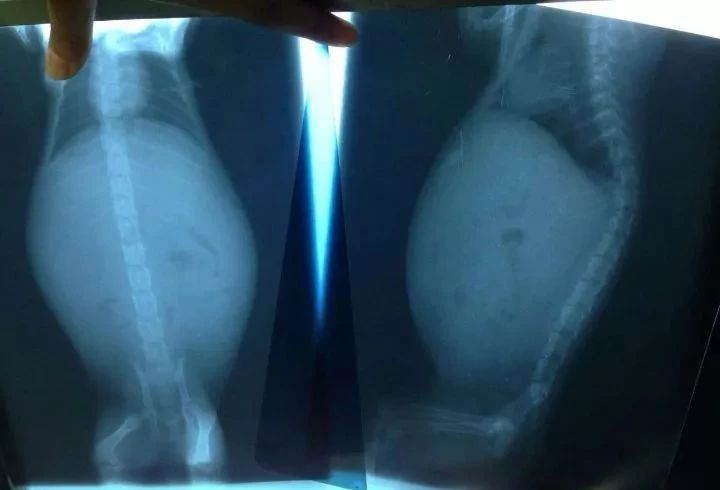

我们前面说到,传腹是因为冠状病毒离开肠道,入侵了其他器官组织,当这些器官组织感受到此病毒的威胁时,免疫系统就会做出过度的反应,然后释放出一些混杂着蛋白质、白细胞和血浆的粘液,储藏在猫咪的肚子里。

所以湿性传腹的猫咪肚子一般都会异常的大。

4.湿性传腹的猫咪肚子会肿胀无比